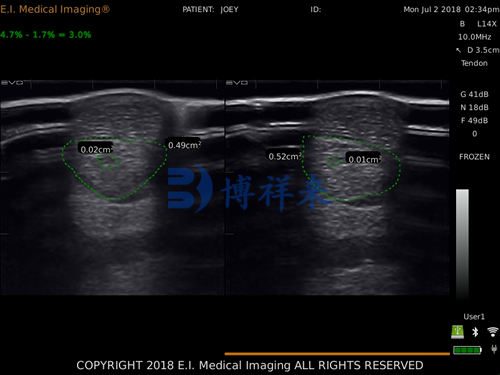

横向切面:用于测量断裂面积、评估出血和液体积聚;

断裂区横截面积变化率(CSA%):持续缩小代表愈合良好;